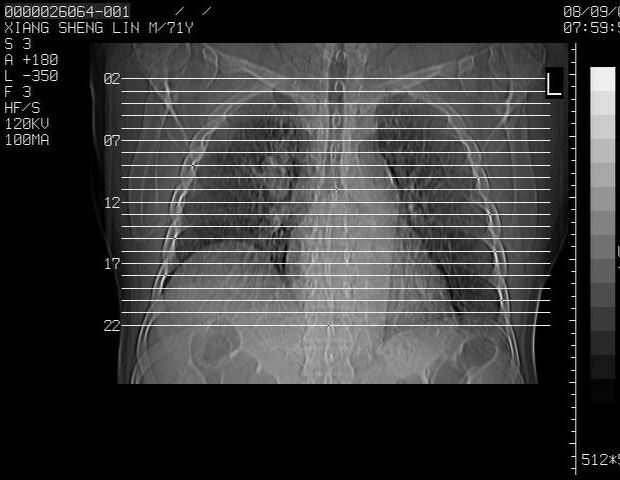

标题: CT15869:男性,71岁,因咳嗽而就诊,请讨论右上肺病变性质 [打印本页]

标题: CT15869:男性,71岁,因咳嗽而就诊,请讨论右上肺病变性质

患者,男性,71岁,因咳嗽而就诊,

1,右肺中心型ca,气管隆突旁淋巴结转移。

2,右膈明显抬高,建议肝脏扫描排除转移或原发灶。